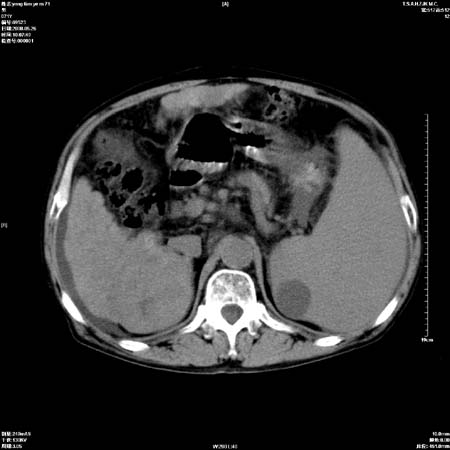

以下是引用医影拾贝在2008-6-5 22:48:00的发言:[br]肝硬化、门脉高压、胃底食管静脉曲张、低蛋白血症(胆囊壁水肿、增厚)、腹水[br]脾功能亢进、脾大、脾、左肾囊肿[br]肝囊性占位、不除外肝脓肿可能[br]建议增强以除外肝右叶肝ca可能

以下是引用chenglinhunan在2008-6-5 22:53:00的发言:[br]1. 肝硬化腹水,脾肿大。[br]2. 肝右后叶占位,肝癌。[br]3。建议ct增强扫描。

以下是引用xulianj在2008-6-5 21:40:00的发言:[br]支持肝硬化腹水;建议增强。肝、脾、肾囊肿待排。

以下是引用zjzjr在2008-6-6 12:34:00的发言:[br]1. 肝硬化腹水,脾肿大。[br]2. 肝右后叶占位,肝癌。[br]3。建议ct增强扫描。[br]4肝脾囊肿.